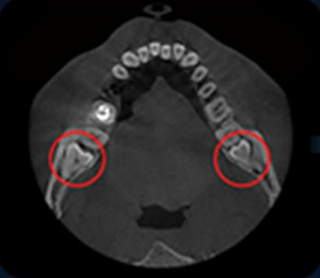

• 3D 구강스캐너

CT 촬영 정밀검진

진단부터 시술까지 디지털화된 데이터로 진행되어 정확하고

수준높은 치료를 쉽게 받으실 수 있습니다.